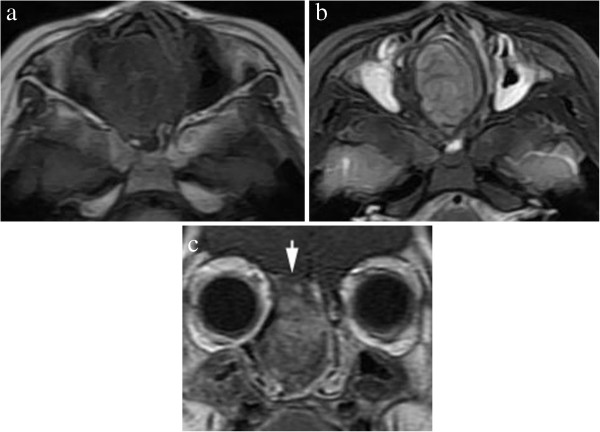

Figure 4.

An axial non-contrast CT revealed an well-defined, irregular, calcified soft-tissue mass in the left nasal cavity.

A 6-week-old girl, born at full term by transvaginal delivery, presented with a 4-week history of left nasal watery rhinorrhea and obstruction. Physical examination revealed a purple polypoid mass in the left nasal cavity. All other findings of her medical and family history were unremarkable. Non-contrast CT scans revealed a 2.6 × 3.4 × 3.9 cm well-defined, expansile mass with amorphous calcification in the left nasal cavity (Figure 4). The mass caused pressure remodeling of the adjacent bones without evidence of destruction or invasion of the adjacent structures. MRI demonstrated that the signal intensity of the mass was heterogeneous on T1- and T2-weighted images. The T2-weighted images further showed multiple round areas of high signal intensity within the lesion. The majority of the mass showed a strongly heterogeneous enhancement and the multiple round areas of high signal intensity on T2-weighted images were demonstrated as non-enhancing cystic components after administration of contrast medium (Figure 5). Total resection of the mass was performed in this patient. Histopathologically, the mass was composed of multiple irregular cartilage islands in mesenchymal elements such as spindle cells in a myxoid stroma. The patient is currently doing well postoperatively, without evidence of residue or recurrence according to a 10-month follow-up CT scan.